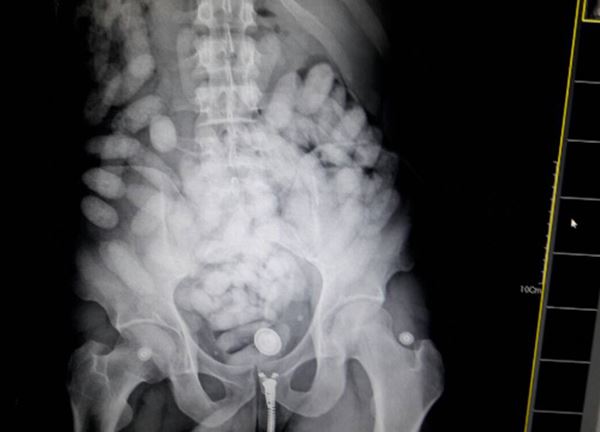

ตำรวจปราบปรามยาเสพติด ร่วมกับ ปปส. ศุลกากร ตม. และตำรวจท่องเที่ยว ร่วมกันจับกุมตัว นายพอโล เฮนรีคิว ไพเรส โด นาสซีเมนโต (MR.PAULO HENRIQUE PIRES DO NASCIMENTO ) สัญชาติบราซิล ผู้ต้องหาลักลอบนำยาเสพติด ประเภทโคเคน จำนวน 100 ก้อน น้ำหนักประมาณ 1,300 กรัม โดยวิธีการกลืนลงท้องแล้ว เดินทางมาจากประเทศเอธิโอเปีย และเจ้าหน้าที่ยังสามารถขยายผลจับกุม นายเอลโซนาส โคลิต้า ดา ซิลวา (MR.COLETA DA SILVA ELSONIAS) ขณะเข้ามารับยาเสพติดภายในห้องพัก

ทั้งนี้ จากแนวทางการสืบสวนของเจ้าหน้าที่ทราบว่า จะมีชายชาวบราซิลลักลอบนำยาเสพติดผ่านช่องทางสนามบิน กับสายการบินเอธิโอเปีย แอร์ไลน์ เที่ยวบินที่ ET 618 วันที่ 6 กันยายน 2560 เวลาประมาณ 20.30 น. พบนายพอโล เดินทางมากับสายการบินดังกล่าว และได้เฝ้าติดตาม กระทั่งผู้ต้องหามารับกระเป๋าเดินทางที่สายพานรับกระเป๋า จึงได้แสดงตัวและเข้าตรวจสอบ พบวัตถุเป็นก้อนกลมรีภายในช่องท้อง เชื่อว่าเป็นยาเสพติด ซึ่งผู้ต้องหายอมรับว่าได้กลืนยาเสพติดดังกล่าวมาจากประเทศบราซิล เจ้าหน้าที่จึงขอให้นายพอโล ให้ความร่วมมือโดยการขยายผลเข้าพักที่โรงแรมบริเวณสุขุมวิท 64 แล้วจะมีคนติดต่อมารับยาเสพติด